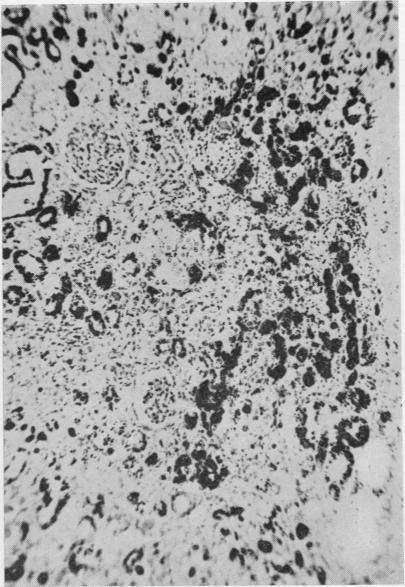

A case of paroxysmal nocturnal haemoglobinuria associated with secondary haemochromatosis, a lower nephron nephrosis, and a megaloblastic anaemia.

J Clin Pathol. 1955 Aug;8(3):211-7. doi: 10.1136/jcp.8.3.211.